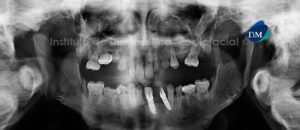

Paciente masculino, 13 años de edad es referido al Instituto de Diagnóstico Maxilofacial (IDM) para evaluación general y por leve molestias en el sector ántero